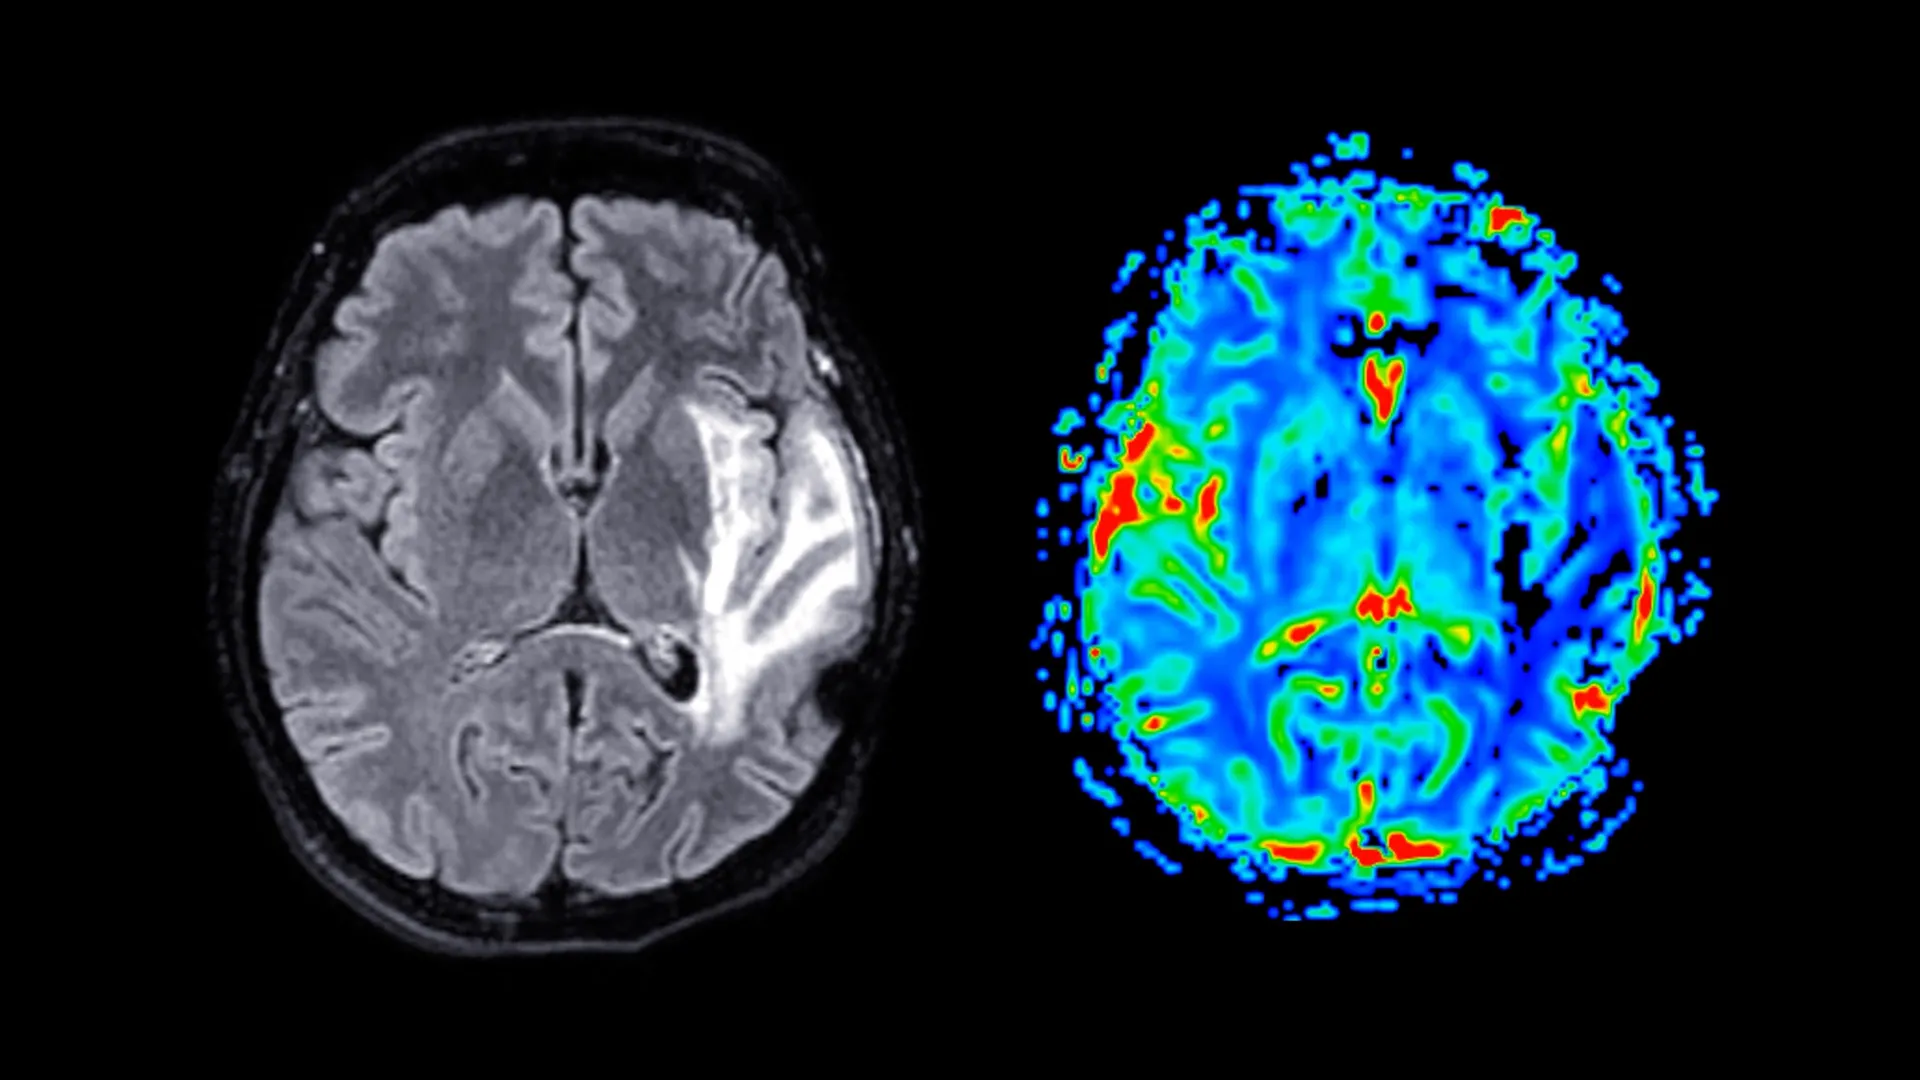

Participants actively engaged in the study by completing detailed questionnaires designed to elicit information regarding their menopausal symptoms, their current psychological state, their sleep habits, and their general health status. A subset of these participants also underwent standardized cognitive assessments designed to evaluate memory function and reaction times. Furthermore, approximately 11,000 women provided consent for magnetic resonance imaging (MRI) scans, a crucial component that enabled researchers to scrutinize structural differences within the brain. The average age at which participants reached menopause was approximately 49.5 years, with those prescribed HRT commencing treatment, on average, around the age of 49.

The neuroimaging data provided compelling evidence of significant reductions in grey matter volume among post-menopausal women, a finding that held true regardless of their HRT usage. Grey matter, the brain’s primary processing hub, comprises neuronal cell bodies and is instrumental in a wide array of functions, including information processing, motor control, and the regulation of memory and emotions. The brain regions most profoundly affected by this reduction included the hippocampus, a structure critically involved in the formation and consolidation of memories; the entorhinal cortex, which serves as a vital conduit for information transfer between the hippocampus and other brain areas; and the anterior cingulate cortex, a region integral to emotional regulation, decision-making processes, and attentional focus.

Professor Barbara Sahakian, the senior author of the study and a member of the Department of Psychiatry, drew attention to the significant implications of these structural changes. She highlighted that the brain regions exhibiting these volumetric differences are precisely those that are characteristically affected in Alzheimer’s disease. This observation suggests that menopause might render these women more susceptible to neurodegenerative conditions later in life. While acknowledging that menopause is not the sole determinant, Professor Sahakian posited that these findings could contribute to explaining the observed phenomenon of nearly twice as many dementia cases occurring in women compared to men.